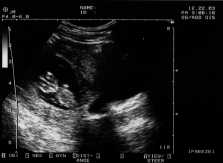

On November 26, we had the first appointment with the Doctor, and got the big news - TWINS!! Definitely the biggest surprise of my life – and it’s still a little surprising every day when I wake up and think to myself – “We’re having twins!!” (The ultrasound at the top right is from our first visit at 7.5 weeks – you can see the two amniotic sacs – amazing!)